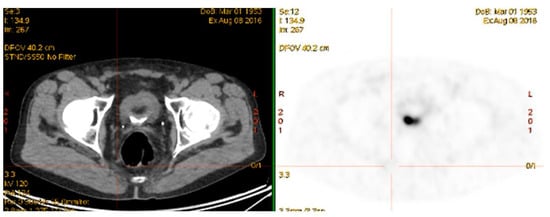

The results with 68Ga-PSMA PET/CT directed external beam radiotherapy in the primary and salvage setting have been encouraging. Several studies have shown a change in radiotherapy planning from 20–60% of patients imaged with 68Ga-PSMA PET/CT prior to external beam radiotherapy [93,94,95]. 68Ga-PSMA PET/CT also has a role post-definitive radiotherapy in detecting site of biochemical relapse. In an Australian study of 419 men treated with external beam radiotherapy, 68Ga-PSMA PET/CT identified all cases of biochemical relapse [96]. This allows potential salvage therapy if the recurrence is outside the previous radiotherapy field, as was the case for the patient in Figure 4. A negative 68Ga-PSMA PET/CT scan in the setting of biochemical recurrence also appears to have prognostic implications for salvage radiotherapy. In a study of 164 Australian men, a negative 68Ga-PSMA PET/CT showed treatment response benefit compared with patients with a positive 68Ga-PSMA PET/CT scan [97]. Although seemingly counter-intuitive, this again reinforces the likely scenario that very small volume/micro-metastatic nodal recurrence is more likely to be amenable to pelvic radiotherapy than disease that is visible on 68Ga-PSMA PET/CT. By this stage the chance of disease having spread outside the confines of the area of the salvage pelvic radiotherapy field, is likely to be high. Whether systemic therapy, combined with either chemotherapy or targeted radiopeptide therapy, together with salvage pelvic radiotherapy can improve response rates in this setting has yet to be elucidated. The long-term outcome of altering treatment planning based on 68Ga-PSMA PET/CT has not yet been addressed in any large longitudinal studies.

Figure 4.

Targeted radiotherapy to recurrent 68Ga-PSMA avid right pre-sacral lymph node. June 2015.

Serial 68Ga-PSMA PET/CT scans have been used to assess the intermediate term outcomes of radiotherapy in recurrent nodal disease [98,99] (Figure 5). These studies show reductions in SUV in most lesions treated, indicating response, however, the responses based on 68Ga-PSMA PET/CT may take several months to be fully realized [99]. Therapeutic response of chemotherapy based on 68Ga-PSMA PET/CT imaging has been poorly studied with only a single paper showing a potential role of this imaging modality with monitoring the effectiveness of docetaxel chemotherapy [100]. This is, however, a growing area of interest as 68Ga-PSMA PET/CT imaging starts taking over the traditional role that CT and bone scintigraphy has had in monitoring chemotherapeutic response in prostate cancer patients [27]. The poor correlation of RECIST to recognized measures of evaluating molecular responses to cancer treatments, such as the European Organization for Research and Treatment of Cancer (EORTC) criteria has been documented [101]. There is a consensus movement within the nuclear medicine community to harmonize quantitative methods to more accurately compare tumor response to treatment, such as with standard uptake values, and using established criteria such as those found in the EORTC [102], and the PERCIST criteria [103]. More specific definitions for interpreting and evaluating responses 68Ga-PSMA PET/CT have also been described [104]. These molecular based evaluation systems will likely replace the antiquated RECIST criteria for assessing therapeutic response in the era of targeted therapies and molecular imaging.

Figure 5.

Monitoring response of targeted radiotherapy by 68Ga-PSMA PET/CT August 2016. (Previous 68Ga-PSMA avid right pre-sacral lymph node treated June 2015—see Figure 4).